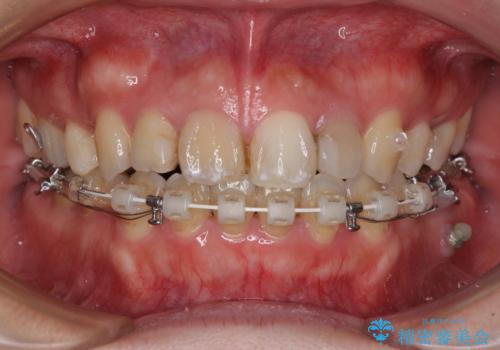

- ハーフリンガル

- 八重歯と前歯のデコボコ、開咬を気にして来院された患者様です。

抜歯矯正が必要であることはご自身で理解されており、目立たない装置をご希望であったので、上顎が裏側装置であるハーフリンガル装置にて治療を行うこととしました。